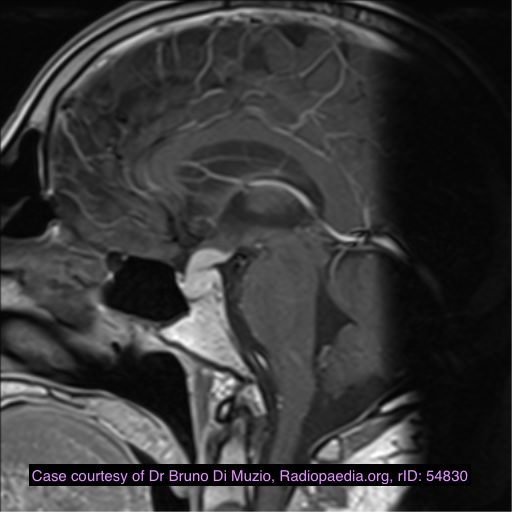

This sagittal T1-weighted MR image shows a suprasellar lesion in a 12 year-old boy. There is a fat-containing area and a cystic area. There was minimal soft tissue component. The lesion expanded and remodelled the sella, without bone erosion. There is elevation of the optic chiasm, and the pituitary can be seen compressed into the base of its fossa.

Case Discussion

The lesion was biopsied. There were epithelial elements, underlying connective tissue with sebaceous glands, and fat, consistent with a mature teratoma. There were no immature or malignant components.

Intracranial teratomas are midline tumours which may contain calcium, soft tissue, cysts and fat. They occur from the optic chiasm to pineal regions. They may be mature, immature or malignant, depending on the degree of differentiation. Differential diagnoses include craniopharyngioma, dermoid and non-germinoma germ cell tumour.